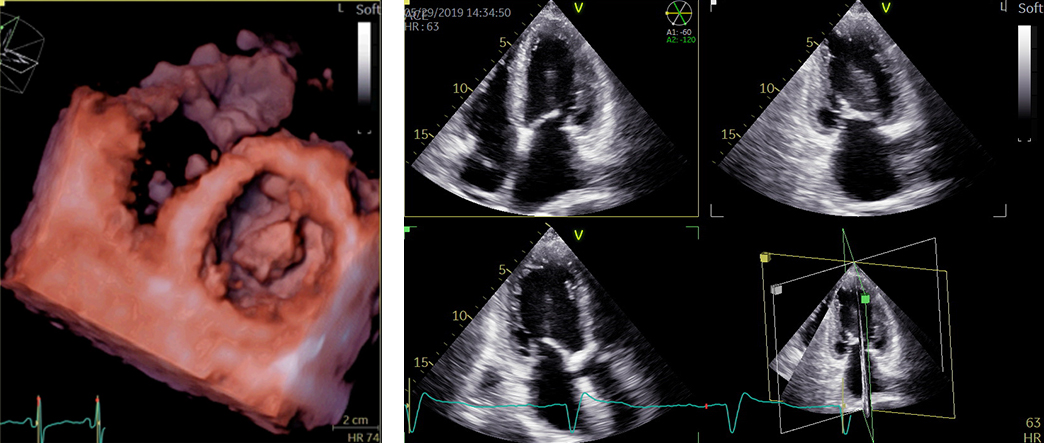

経食道心エコー検査

経食道心エコーは胃カメラとよく似た検査ですが、胃を見るわけではありません。胃カメラと同じような長い管を飲み込んでいただき、超音波を使って食道からすぐ隣の心臓の中を詳細に観察する検査です。心臓の中の構造やサイズが非常に細かくわかるので、この検査でなければ診断がつかない疾患もあります。3D技術がもっとも威力を発揮する検査です。

当院では静脈麻酔を用い、軽く眠っている間に検査を行いますので苦痛はほとんどありません。検査を行うのは医師で、看護師が付き添います。

所要時間は麻酔も合わせて30分〜40分程度です。